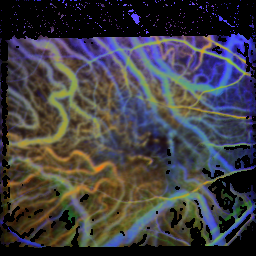

Non-responder

Unfortunately, some shots were stopped before the maximum was reached.

Therefore, it is hardly possible to evaluate them.

| before the first rheopheresis |

| time of the maximum: 93.6 f ± 17.3%visual acuity: 0.25

time of the maximum: 74.1 f ± 14.5%visual acuity: –

time of the maximum: 52.4 f ± 10.1%visual acuity: 0.32

time of the maximum: 66.4 f ± 8.6%visual acuity: 0.20